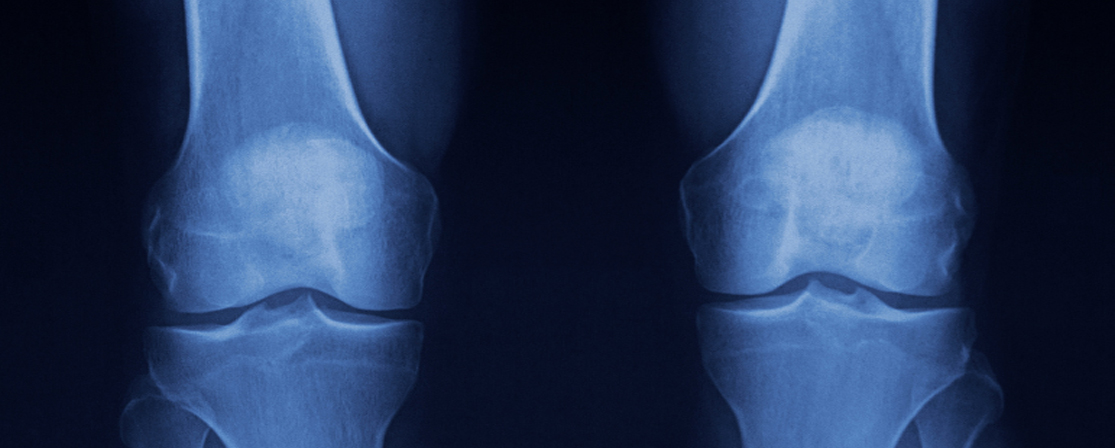

Osteoarthritis in the Knee

What is Knee Osteoarthritis?

Knee osteoarthritis (OA) is a degenerative joint disease that occurs when the protective cartilage in the knee gradually wears down. This leads to pain, stiffness, swelling, and reduced mobility. It is one of the most common causes of knee pain, particularly in older adults.